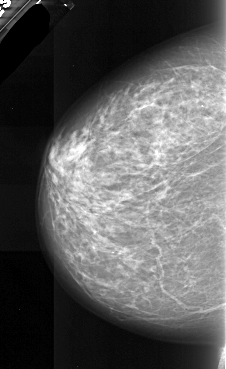

A_1087_1.LEFT_CC

LEFT_CC LINES 5896 PIXELS_PER_LINE 3616 BITS_PER_PIXEL 16 RESOLUTION 42 NON_OVERLAY